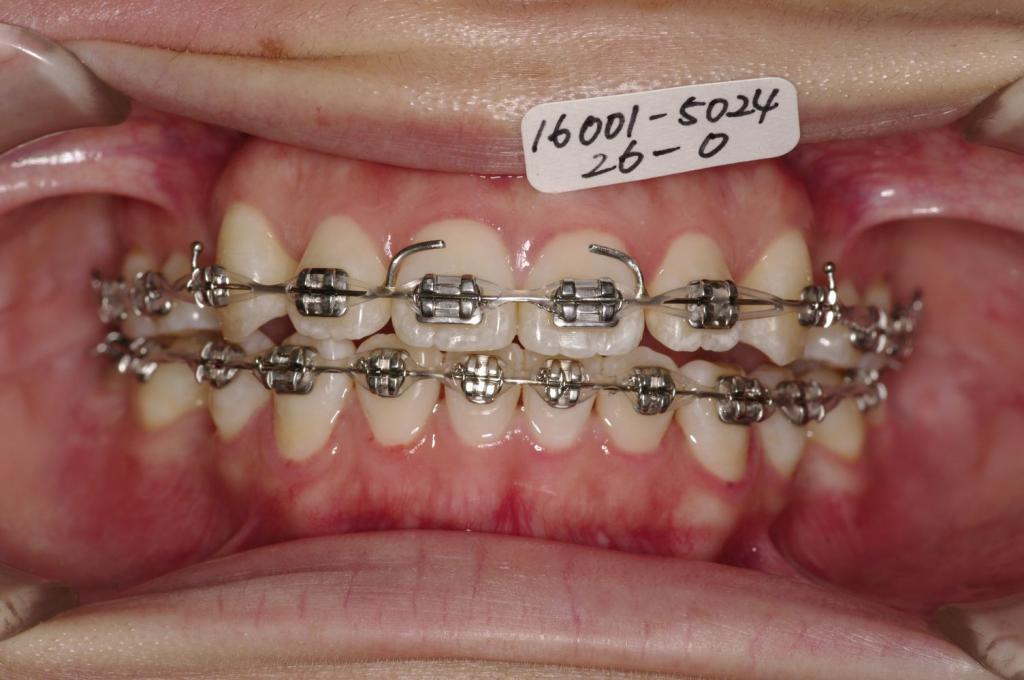

- 上下の前歯の間に舌を入れる癖がある場合には、歯の裏側にフックを付ける場合があります。その場合発音がしにくくなったり、食事の時に舌が痛かったりすることがあります。